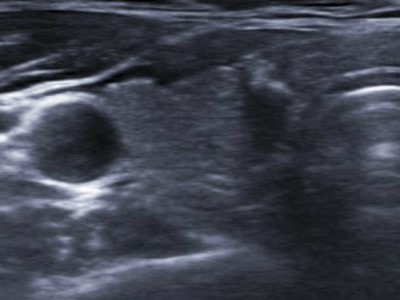

갑상선 석회화 결절의 진단은 갑상선 초음파로 결절의 위치, 개수, 모양, 크기, 내부, 비율, 경계 등을 자세히 관찰하는 것이다. 이로부터 이상이 발견되면 악성의 위험성을 예측할 수 있고 세침흡인세포검사를 시행할 수 있다. 동시에 정상적인 갑상선 기능을 확인하기 위해 혈액 검사를 실시합니다. 그러나 갑상선 초음파에서 갑상선에 석회화된 결절이 보인다고 해서 반드시 갑상선암으로 진행되는 것은 아닙니다. 첫째, 갑상선 결절의 크기가 5mm 이상인 경우 추가 생검이 필요합니다. 그러나 갑상선 석회화가 많이 진행된 경우에는 조직세포 채취에 어려움이 있을 수 있습니다.의정부갑상샘선 김수연유한의원